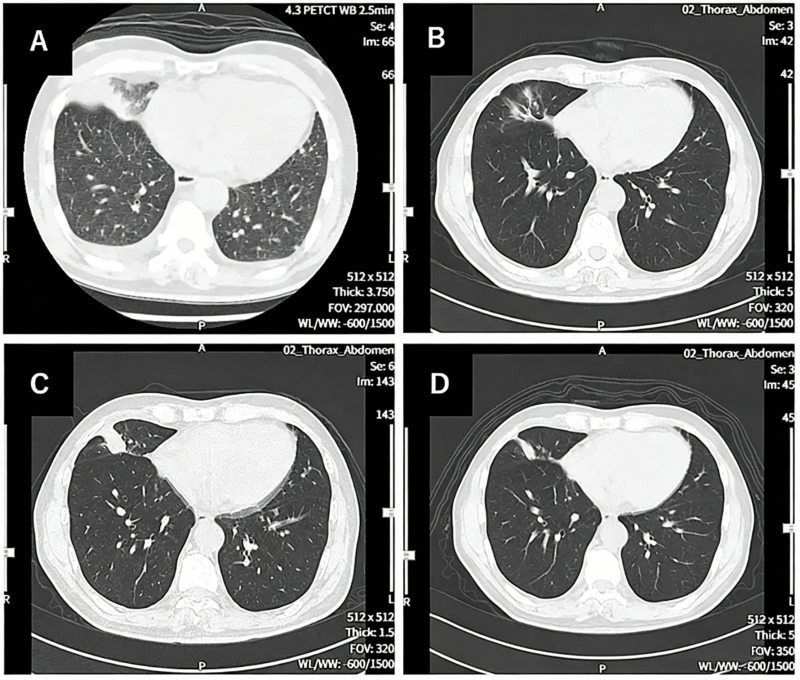

其中一位69岁的晚期非小细胞肺癌患者,经历了多线治疗失败,但在接受3个周期的联合治疗后,右肺的原发病灶基本消失,左肺和纵隔淋巴结的转移灶也显著退缩,达到了临床上的“部分缓解(PR)”。整个过程仅仅出现轻微发热等可控反应。这对于一个终末期患者而言,无异于绝处逢生。

前沿医学的临床转化正在加速。很多上述提到的突破性疫苗及联合疗法,目前正在国内开展严谨的临床研究,如果想更详细的了解,可以将近期的详细病历资料(包括确诊病理报告、基因突变检测报告、最新的影像学CT/PET-CT报告及近期的出院小结等)进行整理,提交至医学部进行初步评估, 多一次问询,或许就能为生命打开一扇全新的窗户。